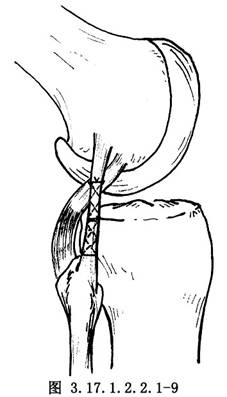

如半月板和交叉韌帶有損傷,儘可能予以修補,然後再自後側開始修補外側結構。①如有後外側關節囊撕脫,將其牽到脛骨關節面下方,用圓針引絲線穿過脛骨關節面下的鑽孔,由前到後縫合固定在脛骨上(圖3.17.1.2.2.1-4)。固定前將脛骨附着部的骨表面弄毛糙,或用骨刀做一新鮮骨創面,以保證後外側關節囊的固定。②有膕肌腱撕裂者,按損傷類型採用不同的方法。股骨附着部的膕肌腱撕裂,常伴有外側副韌帶自股骨上撕脫,可採用Bunnell縫合,通過股骨的鑽孔,捆紮在股骨內上髁的骨面上(圖3.17.1.2.2.1-5)。膕肌腱本身撕裂,將兩端用Bunnell縫合(圖3.17.1.2.2.1-6)。撕裂在肌肉內或肌腱連接部,用Bunnell縫合通過脛骨前外側近端Gerdg結節的骨孔,將肌腱附着到脛骨的後面(圖3.17.1.2.2.1-7)。③修補外側副韌帶。對外側副韌帶的撕裂先明確撕裂的部位,對股骨附着部的撕脫可採用U形釘、螺釘固定,或將斷端用Bunnell縫合,通過股骨的鑽孔捆紮在股骨內上髁上。外側副韌帶從腓骨頂點撕裂則伴有股二頭肌腱、弓狀韌帶及腓側副韌帶附着點的複合撕脫,應一併修復,在腓骨頭穿孔,粗線縫合固定。伴有骨片撕脫,可用1枚螺釘或交叉克氏針固定骨片(圖3.17.1.2.2.1-8)。如爲韌帶本身的撕裂,找出兩斷端拉緊後屈膝30°位,用不吸收的絲線對端或重疊縫合(圖3.17.1.2.2.1-9)。並將外側緣向前推進,縫合在外側正中關節囊的後緣和外側副韌帶的後緣。還可應用股二頭肌腱、腓腸肌腱和髂脛束加強修補。